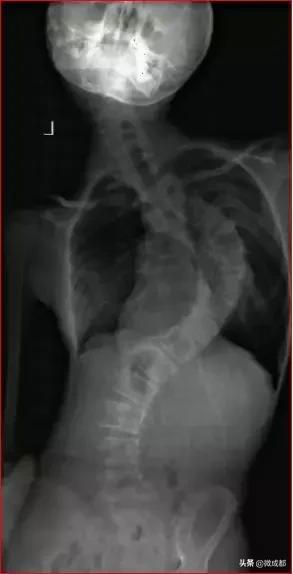

通俗一点说就是,正常人的脊柱应该是一条直线,并且躯干两侧是对称的。如果哪一天你发现从正面看,娃儿有双肩不等高,或者从后面看到有后背左右不平的情况,就应怀疑是不是有脊柱侧弯了。

如果发现这样的情况,家长要及时带娃儿到医院拍摄站立位的全脊柱X线片,如果正位X线片显示脊柱有大于10度的侧方弯曲,就可以诊断脊柱侧弯。

像这个X光片中这样侧弯程度的脊柱是比较少的,但是脊柱侧弯的人却不在少数,尤其父母们总觉得自己的幺幺、乖乖啥子问题都莫得。